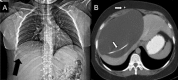

CSF pseudocyst: an unusual cause of back pain